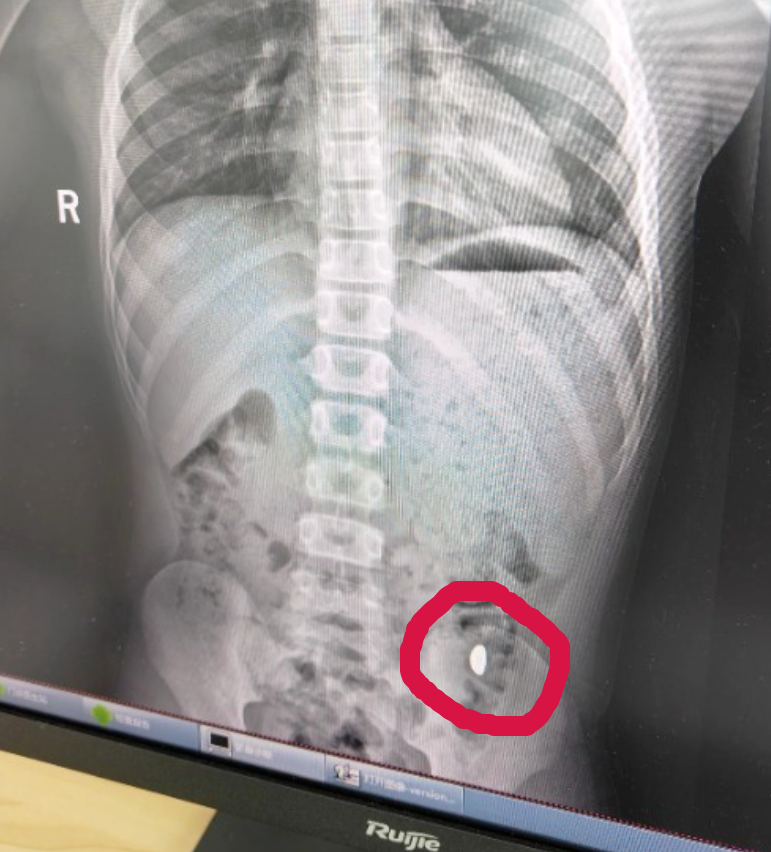

纪女士回忆道:“以前我侄女吞过硬币,去医院后医生说问题不大,能通过大便排出来。我在网上搜了搜,也说金子能排出来,所以就没太在意。我还每天提醒他不能在外面拉屎,因为这屎可有点贵。”可在家等了5天,她对着大便扒拉了两次,都没找到金子。没办法,她只好带“熊孩子”去医院求助。检查发现,孩子胃里确实有异物。

幸运的是,孩子没感觉不舒服。纪女士说:“上午去的医院,下午就拉出来了。”她把这件事发到社交平台,引来了50多万人围观。她提醒大家:“一定要把家里的金子放好,别让熊孩子看到。”